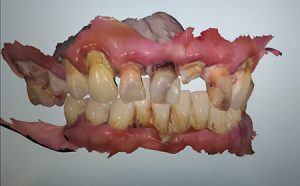

A patient in their fifties lost all their upper teeth due to poor dental hygiene over a long period of time. The patient came in after their tooth number 21 (8) broke and fell out. In the first phase, the upper arch was restored – extractions were performed on the upper arch, implants were placed, and the most suitable multi-units were chosen. For the anterior area, four angled multi-units were selected. As can be seen, the screw channels are parallel and oriented on the occlusal plane after correction. The support of the multi-unit helps predict the angle of the future screw channel. Each angled multi-unit is equipped with such a support.

To determine the VDO (Vertical Dimension of Occlusion) for the patient, impressions were taken twice: the first time before extractions and the second time with the impression abutments. The second impression was placed on top of the first one.